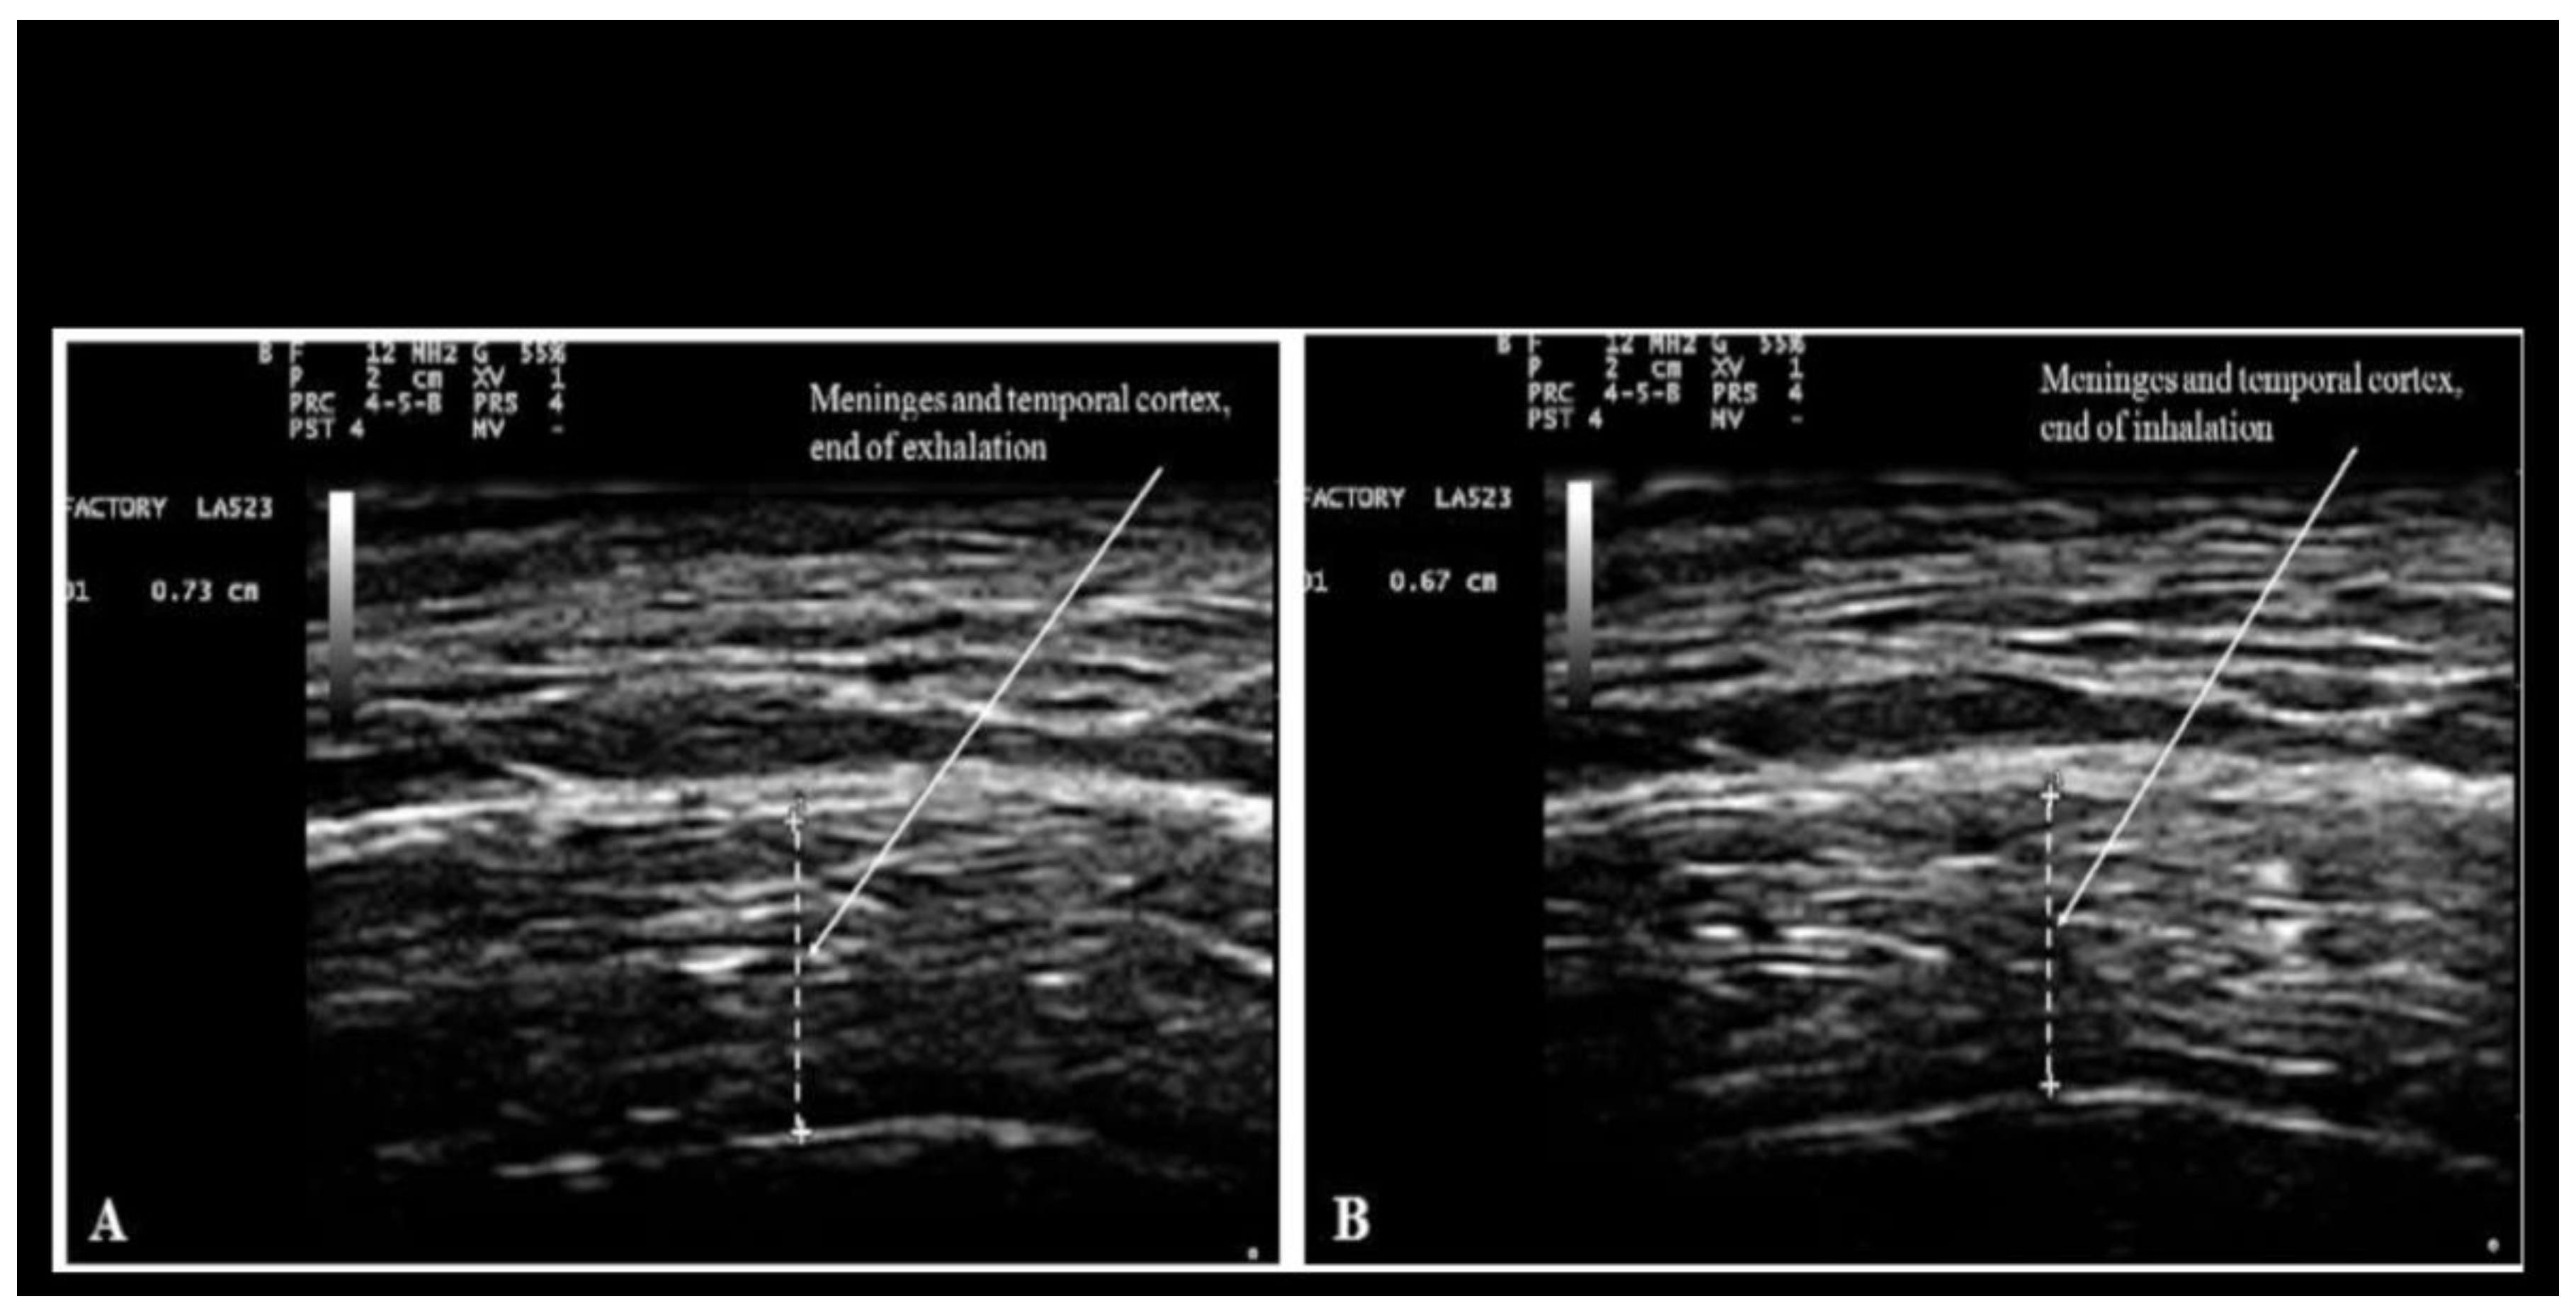

Since the chanting of Nam-Myoho-Renge-Kyo is characterized by a peculiar pattern of respiration with rapid inspiration and prolonged exhalation, the effects of breathing on brain movements are here reported. Morphology of brain structures was previously studied by the author and his colleagues using transcranial ultrasonography as described in Ruggiero et al. (2013); Bradstreet et al. (2014); and Ruggiero (2022). Briefly, transcranial ultrasonography of the temporal lobe of the brain was performed using an Esaote MyLabFive (Esaote, SpA, Firenze, Italy) ultrasound system with a linear probe for muscle-skeletal examination (LA 523 by Esaote). The settings were adjusted for adult transcranial imaging as described in Ruggiero et al. (2013). The probe was positioned onto the temporal region of the head corresponding to the squama of the temporal bone, gently tilting it until the hyper-echoic line corresponding to the squama of the temporal bone was horizontal. The results depicted in Figure 1 were obtained at the Department of Human Anatomy, Histology and Forensic Medicine of the University of Firenze, Italy. These images are here reported, and their significance discussed, in the context of the object of this article. Figure 1 below is reproduced from Ruggiero et al. (2013) under the terms allowed by Firenze University Press. The rationale for investigating brain movements stems from the observation that breathing-induced alterations in brain water content influence sound wave propagation. Since the speed of sound propagation is directly related to the medium's water content, these transient changes in brain hydration modulate the transmission of sound waves within the brain.

The author's brain activity in the Brodmann area 10 of the prefrontal cortex increased by 11% during the 5 min neurofeedback training session performed before chanting. Such an increase is typical for non-trained subjects. In the session performed during chanting, however, the increase of brain activity in the prefrontal cortex was very modest (3%). Conversely, a large increase (52%) of brain activity in the prefrontal cortex was recorded in the session performed immediately after chanting. The results concerning the increase following chanting are consistent with previous studies demonstrating that meditation enhances blood flow in the prefrontal cortex (Tang et al. 2015; Moss et al. 2022). The results concerning the relative decrease observed during chanting are consistent with the fact that chanting induces a state of focused attention that leads to a decrease of blood flow to brain regions associated with mind wandering or external stimuli processing. Chanting might induce a shift towards slower brainwaves, such as theta waves that could explain the decrease of blood flow in the prefrontal cortex. For a thorough understanding of the processes associated with chanting, changes of brain activity have to be integrated with changes of brain water content occurring while breathing. As mentioned above, chanting of Nam-Myoho-Renge-Kyo is characterized by rapid inspiration and prolonged exhalation and it was demonstrated that the combined thickness of the meninges and cerebral cortex is greater during exhalation (Figure 1). Careful analysis of echogenicity shows that also the water content of the cortex is greater during exhalation. The amount of water in the brain during chanting is further augmented by the increase in blood flow that is associated with brain activity as it is detected by the Mendi device. Therefore, during chanting sound waves travel through the brain for a longer distance, with a faster speed, and greater energy. The increase in speed propagation is due to the fact that myelin, that is responsible for echogenicity, is denser than water. The increase in energy is due to the fact that the energy of a sound wave is related to its intensity, which can be understood as the amount of sound energy flowing through a unit area per unit time. Intensity is directly proportional to the square of the wave's amplitude. The amplitude refers to the maximum displacement of the particles in the medium from their rest position as the wave travels through. For a sound wave to travel faster, the particles in the medium need to be displaced more from their rest positions (larger amplitude). This larger displacement translates to a higher intensity, which signifies more energy carried by the wave. Since sound waves are known to modulate the expression of a number of genes in eukaryotic cells (Kumeta et al. 2018), it may be hypothesized that the greater content of water enhances the known beneficial effects of sound waves (Bartel and Mosabbir 2021) on the brain. It may be worth noticing that the effects of sound waves on the brain are independent of the sense of hearing since bone conduction transmits sound waves to the brain (Henry and Letowski 2007). In particular, sound waves generated in the larynx resonate in the oral and nasal cavities and the sinuses. They reach the brain through the thin bones of the floor of the skull that have sinuses and foramina i.e. the sphenoid and the ethmoid.

Figure 1. Measurement of combined thickness of the meninges and the cortex of the temporal lobe at the end of forced voluntary exhalation (A: 7.3 mm), and inhalation (B: 6.7 mm).